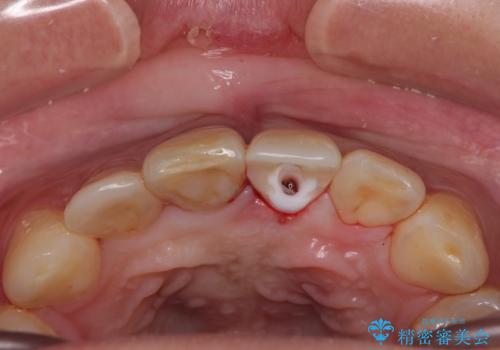

- 転倒により前歯を失ったところにインプラント治療を受けたいとのことで来院された患者様です。

転倒を機に矯正治療を行ったようで、歯列が整い、インプラントのスペースができたとのことで受診をされました。

骨量は十分にあったため、インプラント埋入後速やかに仮歯を装着して、歯肉治癒後にオールセラミッククラウンによる補綴治療を行うこととしました。